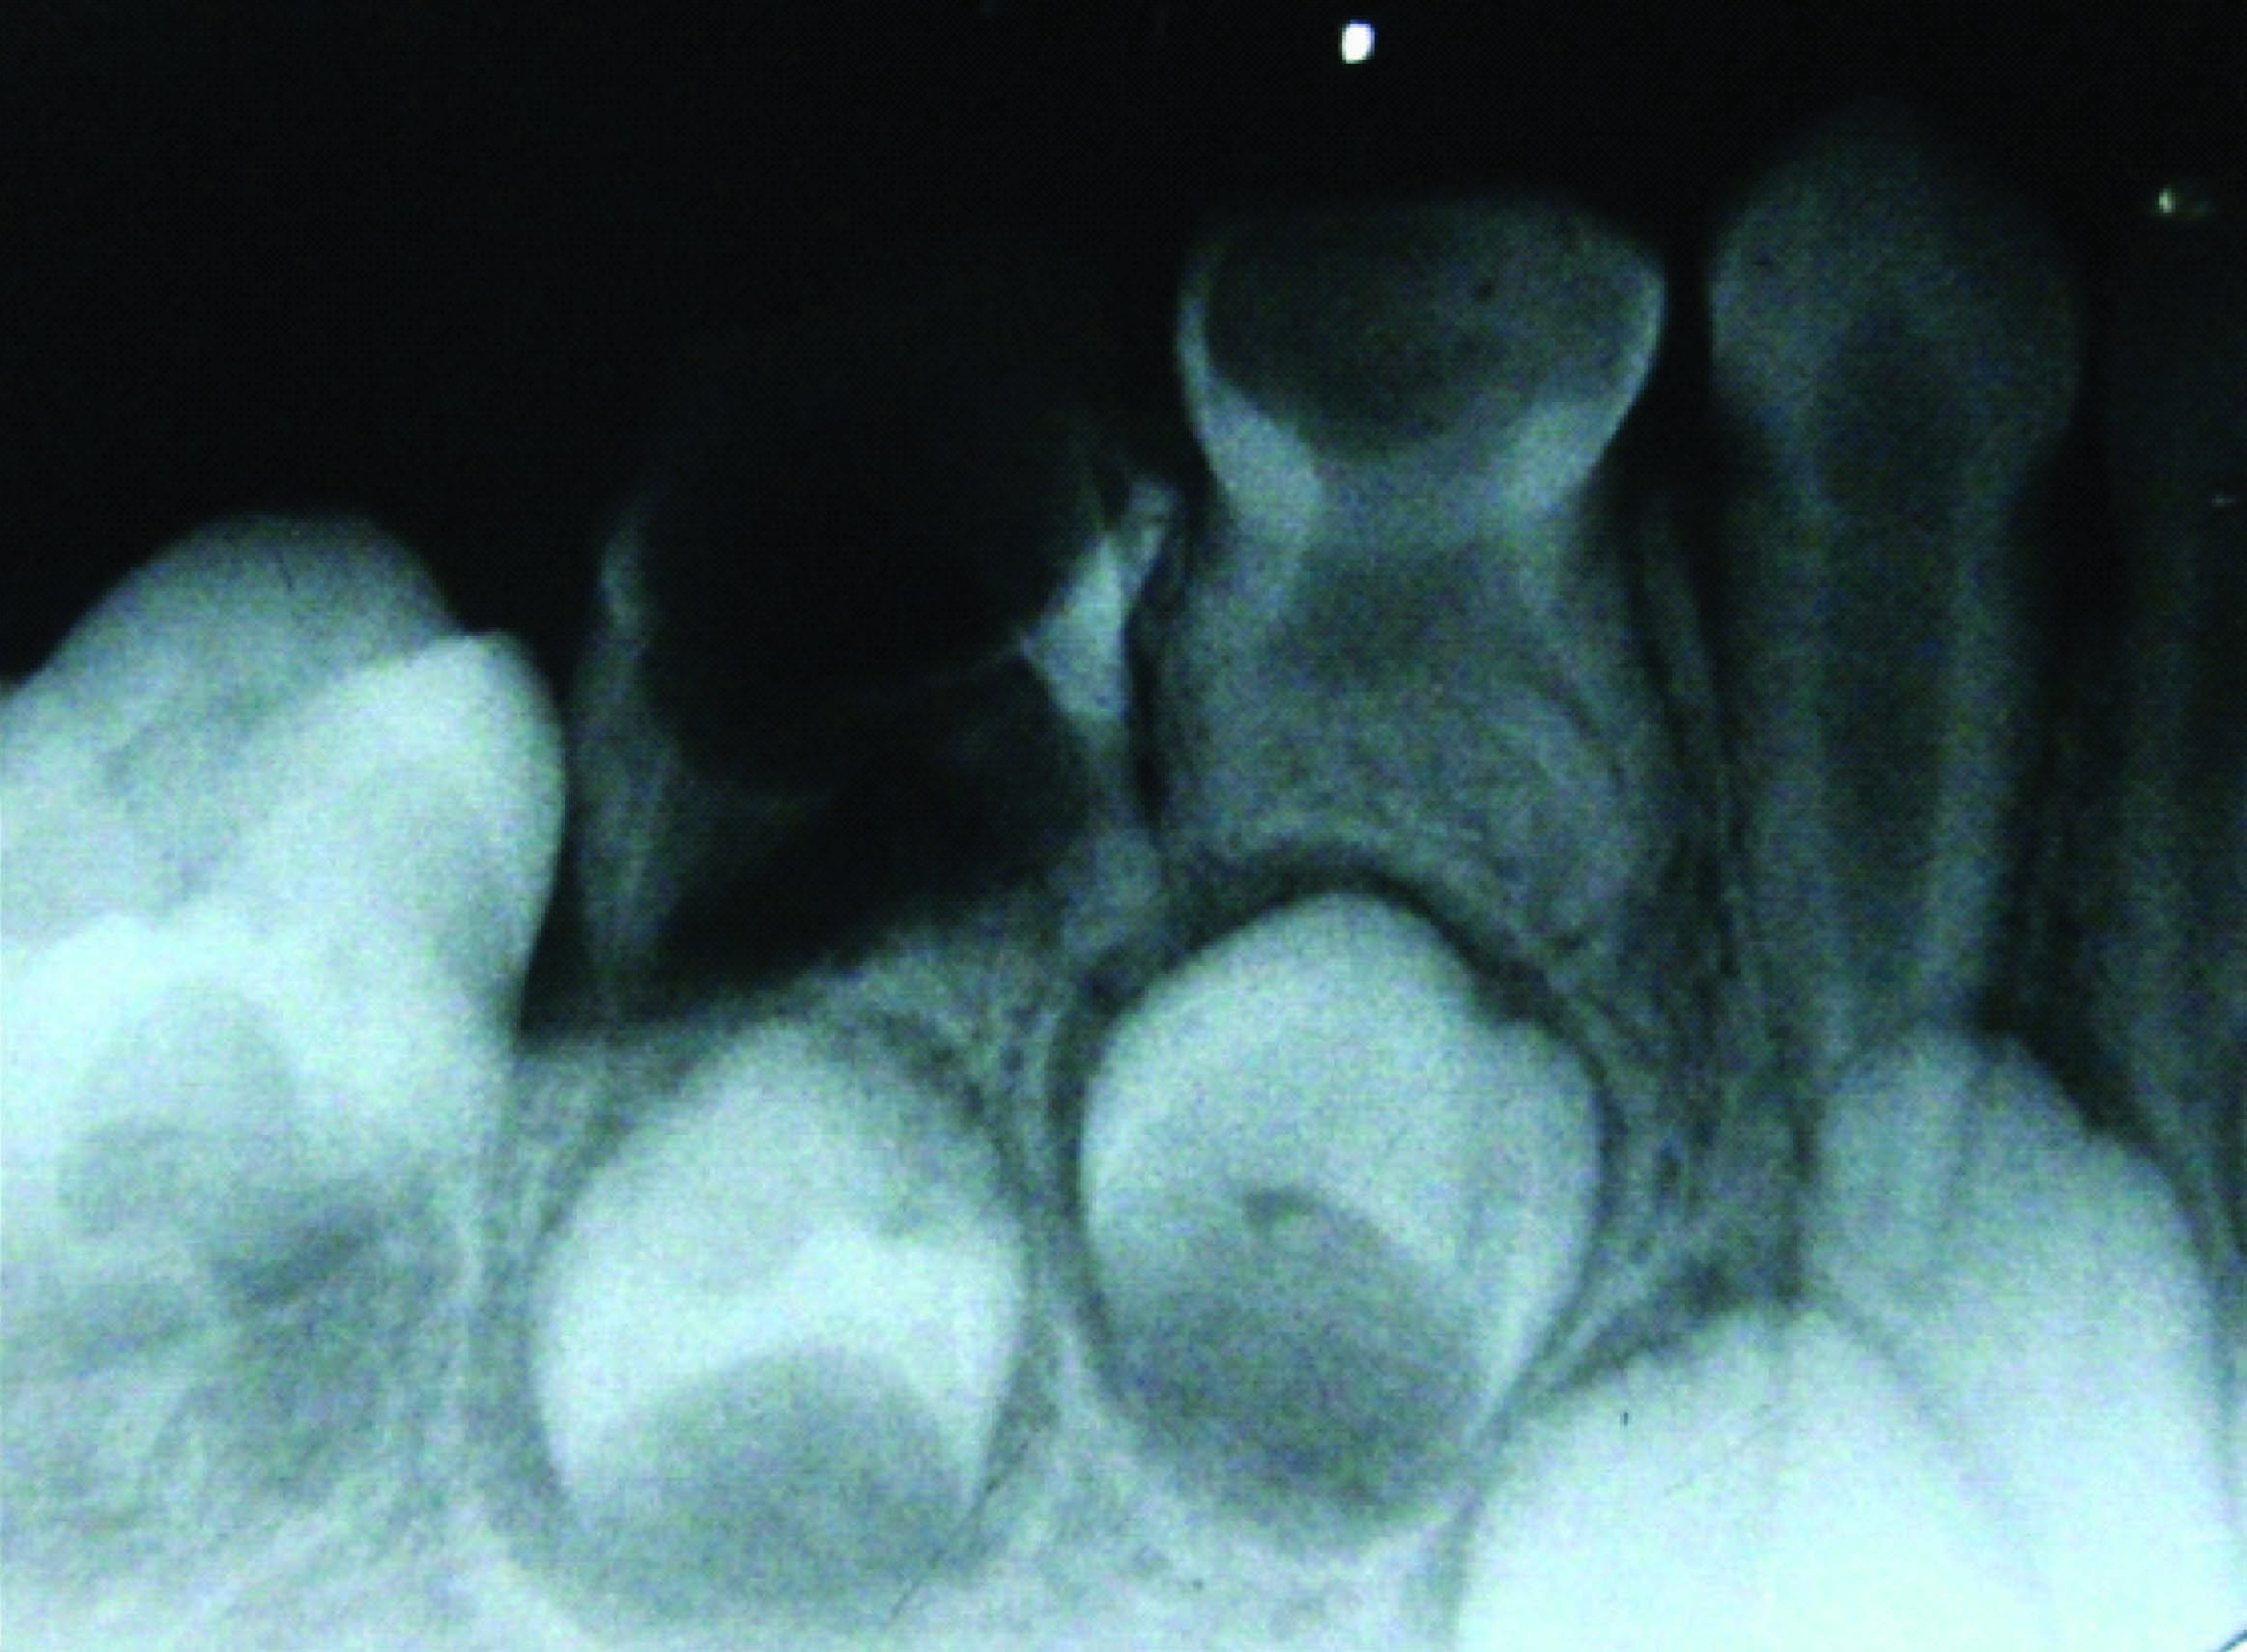

On clinical examination there was deep carious lesion in relation to 74 and 84 and grossly destroyed 64 and 85. Intraoral periapical radiograph of 74 and 84 revealed radiolucency involving pulp and enlarged pulp chamber with short roots suggestive of taurodontism [Table/Fig-1,2]. The teeth were subjected for clinical tests and diagnosis of chronic irreversible pulpitis was made in relation to 64, 74, 84, and 85. The teeth 74 and 84 were treated by multivisit pulpectomy procedure. Obturation was done with vitapex followed by semi permanent restoration with stainless steel crowns [Table/Fig-3].

Preoperative IOPA shows large pulp chamber suggesting taurodontism of 74